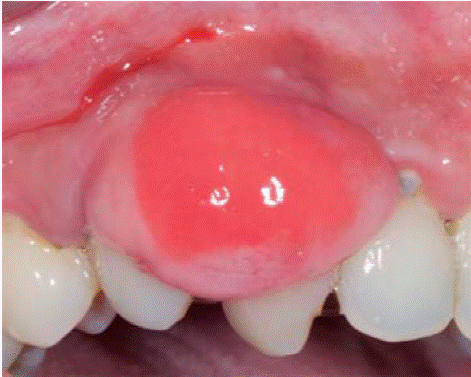

Controles: después de una semana se observó reducción del volumen de la lesión, sin embargo, persistía la coloración rojiza en la zona, por lo cual se mantuvo en observación. Después de seis meses presenta recurréncia de menor intensidad (7x7 mm) (Figura 15). Además se observa presencia de placa obteniéndose un índice de higiene oral (O'Leary) del 52%. Se realiza nuevamente una sesión de instrucción de higiene oral, remoción de placa y por segunda vez la escisión de la lesión. En esta intervención se eliminó mayor margen de tejido aparentemente sano, llegando a remover el periostio adyacente a la lesión.

Durante los siguientes controles la evolución fue favorable, manteniendo mejores niveles de higiene oral y sin presentar recurréncia de la lesión hasta un periodo de seguimiento de siete meses (Figura 16).